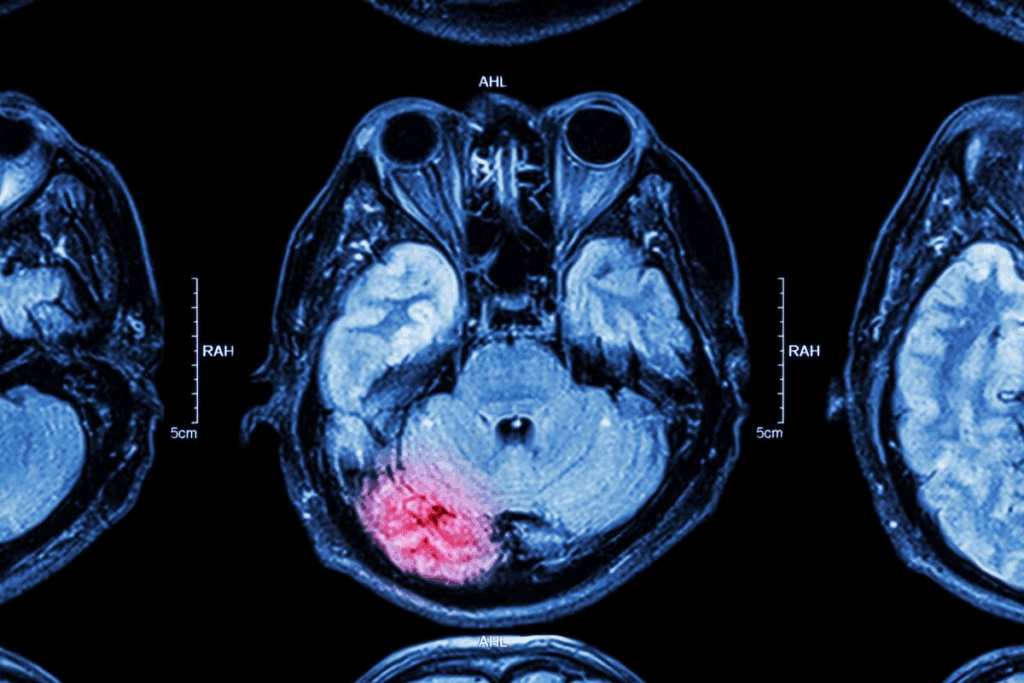

Whether MRI can show leukemia is a complex question. It involves understanding MRI’s strengths and weaknesses. MRI is a key tool in medicine, giving detailed images without harming the body or using harmful radiation.

How MRI Technology Works

MRI uses a strong magnetic field and radio waves to show the body’s inside. When someone has an MRI, they sit in a big magnetic field. This field aligns the hydrogen in their body.

Then, radio waves disturb these aligned hydrogen nuclei. The MRI picks up these signals and makes detailed images. This is great for seeing soft tissues, like organs and tissues affected by leukemia.

MRI’s high-resolution images help doctors see how far the disease has spread. They can also check if treatments are working.

What MRI Can Detect in Leukemia Patients

In leukemia patients, MRI can spot changes in the body. It can see enlarged lymph nodes or spleen, which often happen in leukemia. MRI also finds bone marrow infiltration, where leukemia cells replace normal bone marrow.

• Detecting changes in lymph nodes and spleen size

• Identifying bone marrow infiltration

• Visualizing the extent of disease spread

Limitations of MRI for Leukemia Detection

Even though MRI is powerful, it has limits for finding leukemia. It can’t always tell leukemia apart from other bone marrow or lymph node issues. Also, MRI scans can be expensive and hard to get.

Yet, MRI is very useful in fighting leukemia. It works best when used with other tests like blood tests and bone marrow biopsies.